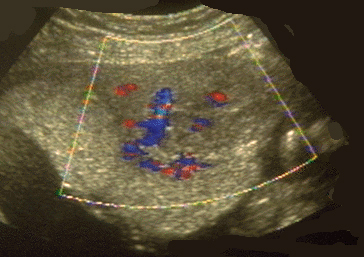

Utérus gravide ; Myome antérieur, vascularisation